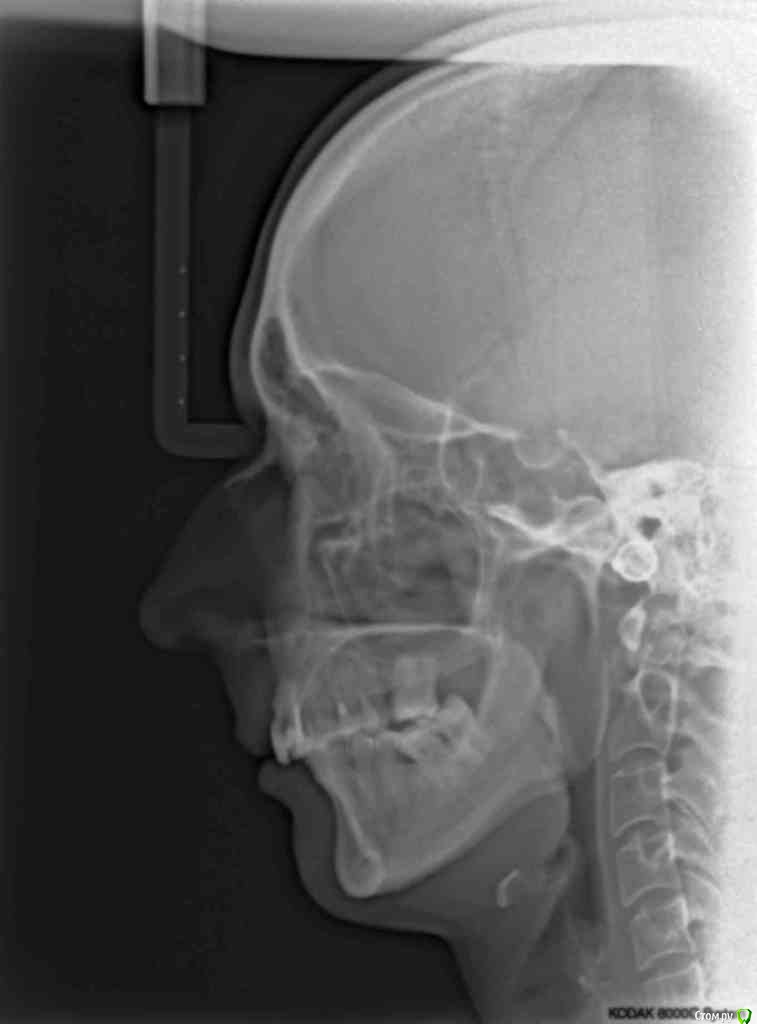

VVQW Опубликовано 6 декабря, 2016 Поделиться Опубликовано 6 декабря, 2016 В результате некачественной ортодонтии более 10 лет назад имеется такая картина. Посоветуйте что-можно сделать?Верхние 6-ки удалены перед брекет системой, по решению ортодонта. Верхние 8-ки не выросли, нижние 6-ки - удалены в подростковом возрасте до 14 лет. http://s019.radikal.ru/i639/1612/56/1345f17db908.jpg http://s019.radikal.ru/i630/1612/55/145ef7c813b2.jpg http://s017.radikal.ru/i440/1612/c2/74bd4da2643e.jpg http://s008.radikal.ru/i303/1612/b4/e80683ed7d2b.jpg http://s010.radikal.ru/i314/1612/74/6d2f9671b0d5.jpg http://s018.radikal.ru/i502/1612/97/9a15fcf4ddd3.jpg http://s020.radikal.ru/i715/1612/59/9bb4a006621f.jpg Ссылка на комментарий

VVQW Опубликовано 6 декабря, 2016 Автор Поделиться Опубликовано 6 декабря, 2016 Добрый день. Беспокоят клиновидки и их прогрессирование из-за неправильной окклюзии.Которая из-за неккоректно проведенного ортодонтическлго лечения. Одно из мнений ортодонтов, 50/50, что надо провести повторное лечение и восстановить зубной ряд имплантами. Вот только дальше варианты у всех свои. Если в верху подвинуть 7 к 5, есть место для импланта? Кость позволит? И наоборот если сделать место под 6, можно ли туда импоант поставить? Спасибо. Ссылка на комментарий